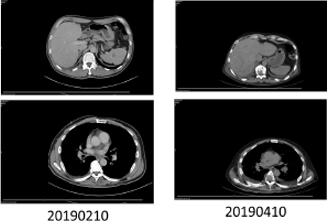

User Story #2

Patients with Lung Cancer Due to Exon 19 mutation in EGFR

- Exon 19 deletion was detected from patient’s tissue using qPCR

- Deletion was confirmed using patients’ blood sample using MoDEL™